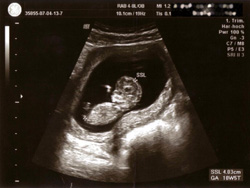

Ultraschall in der Schwangerschaftsbetreuung

• zur Überwachung des normalen Größenwachstums des Kindes

• und zum Ausschluss von Fehlbildungen

Ultraschall in der Schwangerschaftsbetreuung. Das Bild zeigt einen Fötus im Mutterleib.